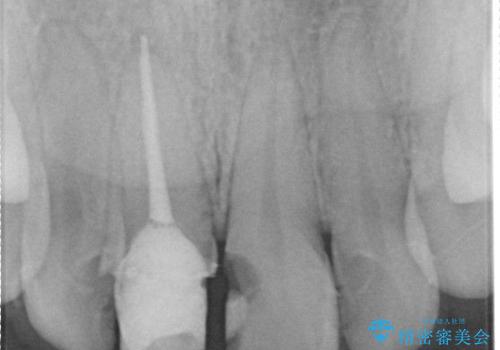

- 他院で治療した前歯の色が気になるということで来院された患者様です。前歯に色の差があり、レントゲンから内部にう蝕も見られたため、審美性に優れ、う蝕になりにくいオールセラミッククラウンで治療いたしました。